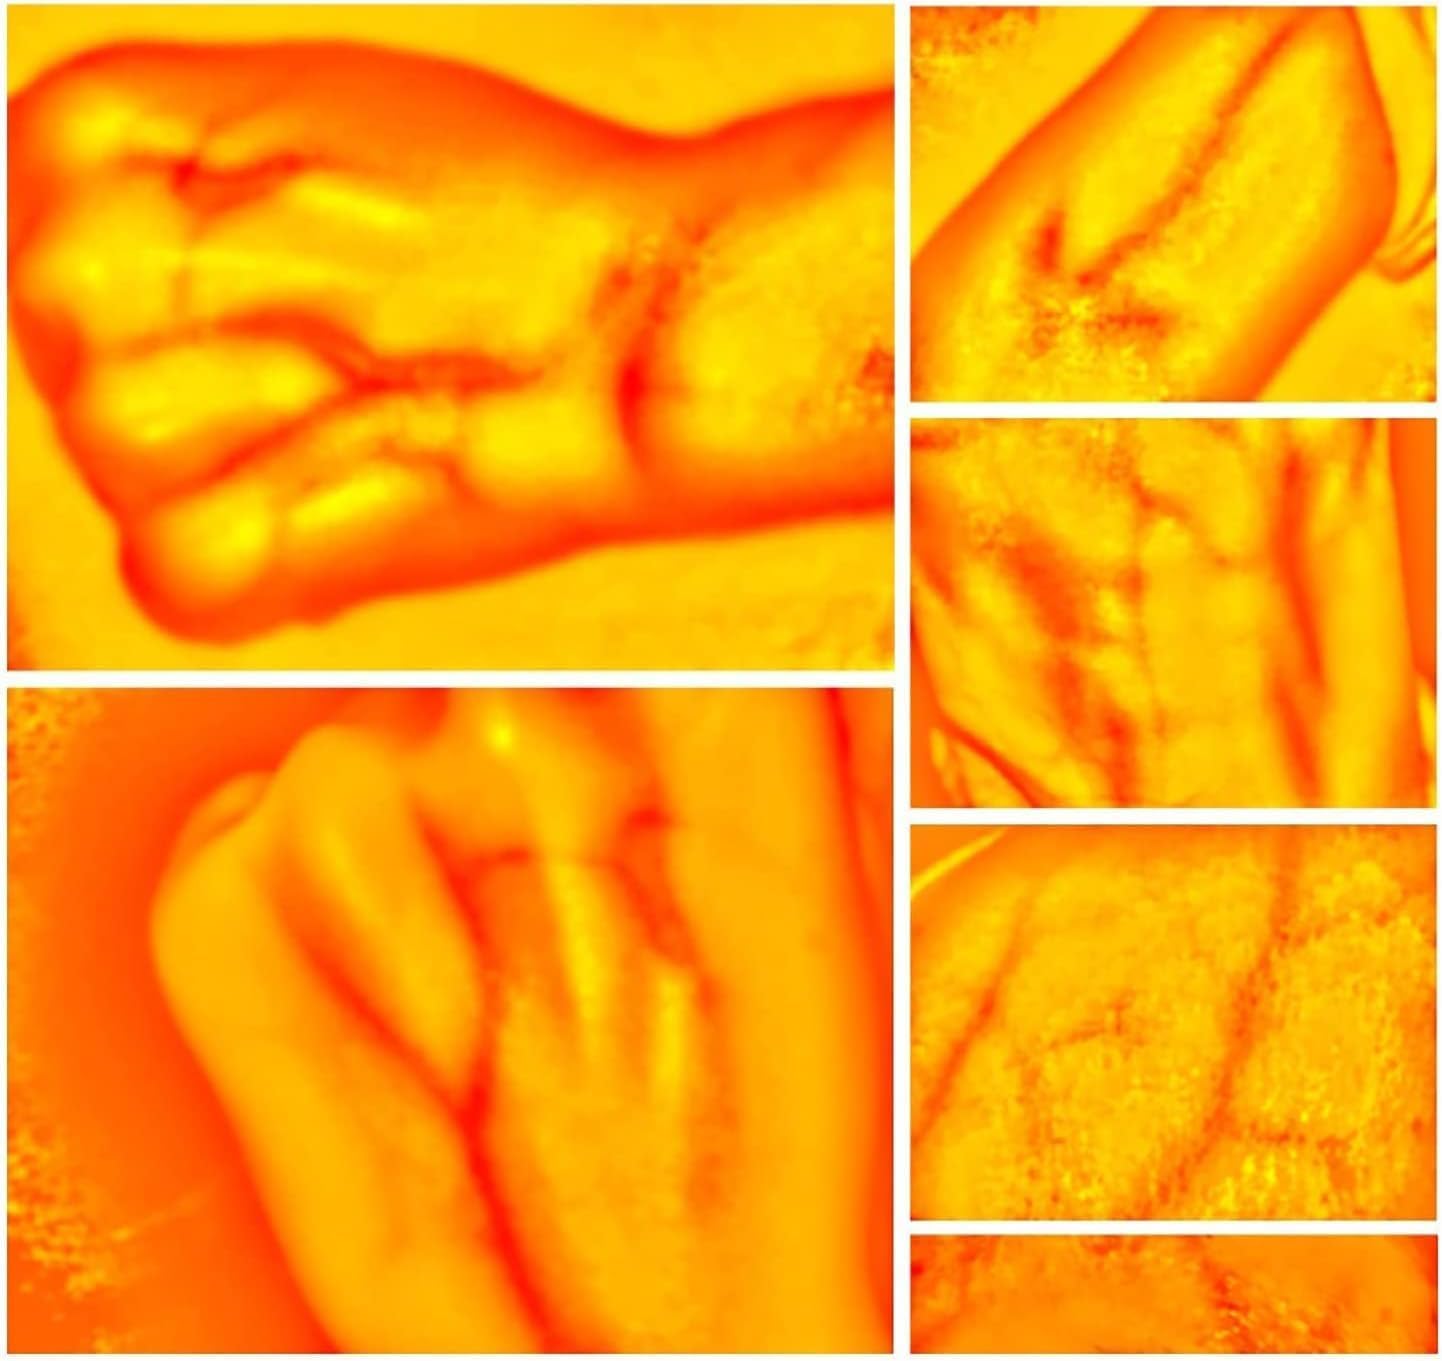

Our medical vein finder device adopts the principles of hemoglobin strong absorption of infrared light,

designed the helpful vein finder device, which consists of infrared vein collector & vein recognition system